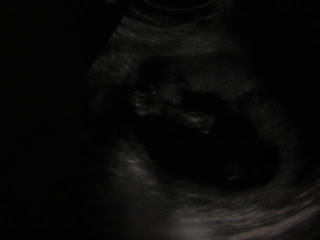

"Yea, it's a little boy! There's the boy parts!" And she drew and arrow for me and spelled it out.

And that, my friends, is our little boy's...well.. boy part.